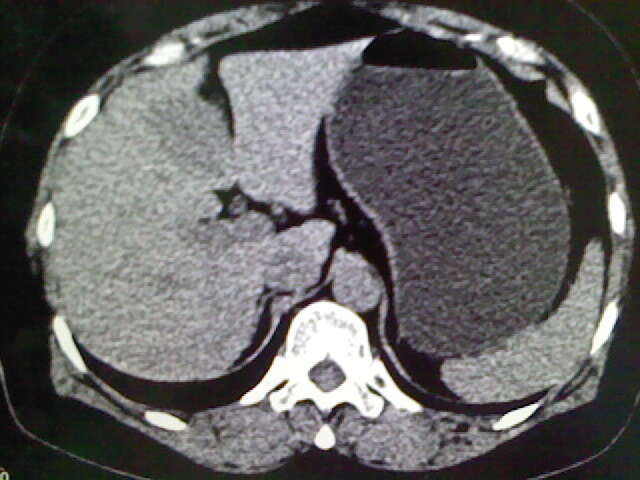

以下是引用卜一在2009-4-2 13:26:00的发言:[br]胆囊颈部结石伴胆囊炎!另:建议增强,待除外肝内占位及胆囊占位!

以下是引用liaoqiang在2009-4-2 16:23:00的发言:[br]胆囊是否切除?胆囊颈区致密影考虑金属夹?结石?肝脏右叶低密度影,考虑增强。